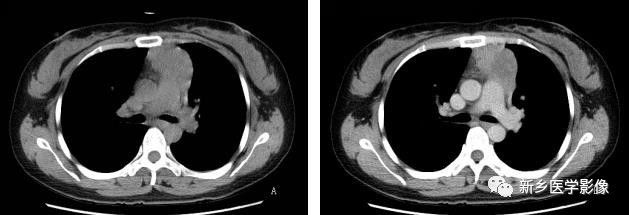

侵袭性胸腺瘤CT图像

a. CT平扫示肺动脉与胸骨间肿块,密度尚均匀,形态不规则b. CT增强示肿块不均匀强化,见低密度囊变区域,肿块与肺动脉之间脂肪间隙消失,肺动脉壁模糊。